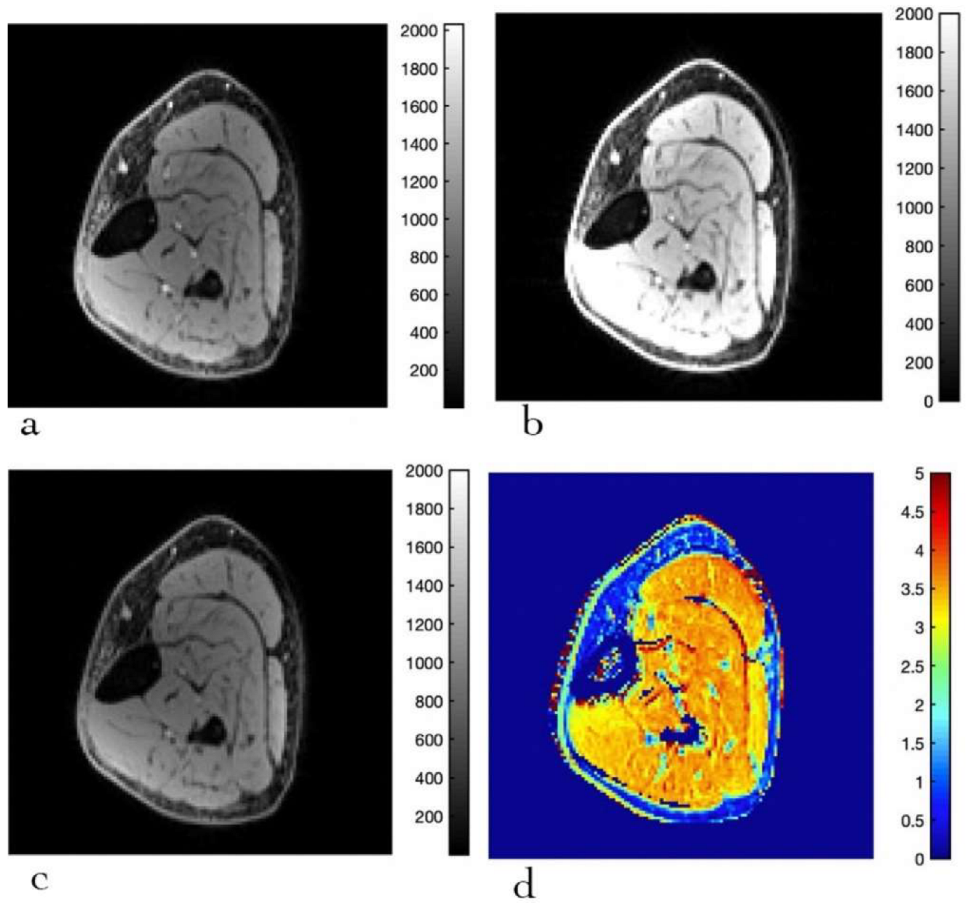

2.3. Computation of T1 and MTsat Maps

3.3. MTsat Mapping